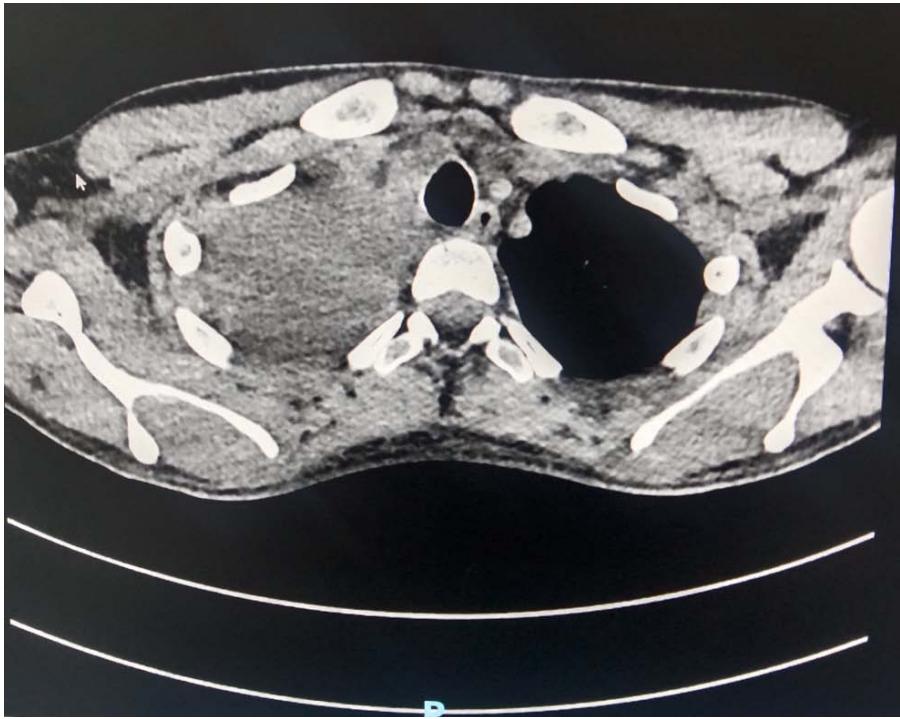

Dr. Parli Raghavan Ravi et al. Massive Hemothorax Following Ultrasound-Guided Central Venous Catheterization in an Anesthetized Patient: A Case Report